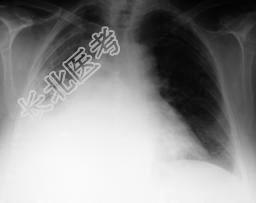

- 单项选择题男,54岁, 发热、胸痛一月余,继往有酗酒史, 请结合CT图像选择最可能的诊断 ( )

A、脓胸

B、肺脓肿

C、大叶性肺炎

D、肺囊虫病

E、肺癌